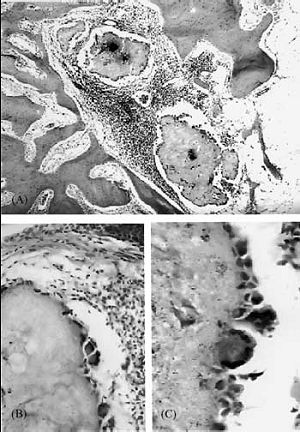

Nine root canals were filled with in the root canal system and two were overfilled with Endomethasone. In six of the nine cases without overfilling, no inflammatory tissue reaction was detected. In three additional cases, mild lymphocytic/plasmocytic infiltration was observed. In both the cases that were overfilled with Endomethasone, moderate to severe lymphocytic/plasmocytic infiltration and granulomatous reaction around the sealer particles were detected. In the granulomatous reaction, epitheloid and foreign body-type giant cells sharply demarcated the sealer particles from the periapical tissue (Fig. 2).

Figure 2. Periapical tissue reaction in root canal over filled with Endomethason.

(A) Lymphocytic/plasmocytic and giant cell infiltration around sealer particles.

(B, C) Foreign body giant cells and epitheloid cells separate the sealer from the periapical tissue.

In six root canals filled with Endomethasone, no inflammatory reaction was detected; however, in the other three cases, Endomethasone initiated chronic lymphocytic/ plasmocytic infiltration. The occurrence of periapical inflammatory reactions initiated by Endomethasone in correctly filled root canals has already been demonstrated in nonhuman primates (Crstavik & Mjor1992). Because sealers within the canal have minimal direct contact with the periapical tissue through the apical foramen, the periapical tissue injury may be related to the release of a certain component of the sealer rather than to direct toxicity. Vajrabhaya & Sithisarn (1997) and Leonardo et al. (1999) suggested that the chemical nature of Endomethasone could be responsible for the inflammatory reaction because the paraformaldehyde content of the sealer was relatively high and it released formaldehyde after setting. The tissue reactions initiated by Endomethasone in overfilled root canals were completely different. Endomethasone initiated a foreign body-type granulomatous reaction where giant cells and epitheloid cells were apposed to the surface and encompassed the sealer. Because sealer particles were not present in the macrophages, it seemed that Endomethasone particles were large enough to preclude phagocytosis by a single macrophage and therefore the giant cells demarcated them from the periapical tissue. This finding suggests that Endomethasone is a relatively inert foreign body that initiates granulomatous reaction. From these observations it seems that Endomethasone initiates inflammatory reactions through multiple pathways. It is possible that Endomethasone has a toxic effect based on the paraformaldehyde content and initiates a chronic granulomatous reaction based on the foreign body nature of the sealer.